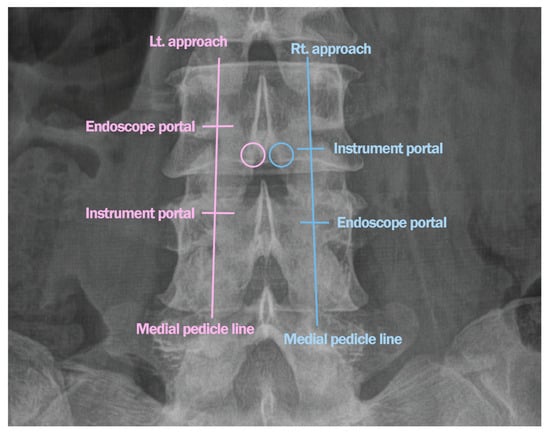

Surgical Technique

2.1. Case 1: Bilateral–Contralateral Decompression in Upper Lumbar Stenosis

2.2. Case 2: Bilateral–Contralateral Decompression in Adjacent Segmental Stenosis (ASS) After Lumbar Fusion

2.3. Case 3: Bilateral–Contralateral Decompression in Spondylolisthesis